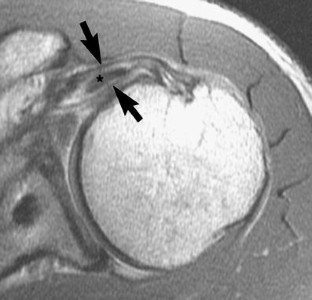

This study was reviewed and approved by our Institutional Review Board. The reports of 548 consecutive MR examinations of the shoulder were reviewed, looking for mention or description of delamination tears of the rotator cuff. The images of the identified cases were then reviewed by two radiologists to confirm the findings. Correlation with surgical and arthroscopic information was then performed. Delamination tears were defined as horizontal retraction of either the bursal or articular surface of the tendon, manifest as thickening of the torn retracted edge, and/or interstitial splitting of the tendon, manifest as fluid-like high signal intensity on fat-suppressed T2-weighted oblique coronal images.

Results

Fourteen cases of delamination tears were identified in 13 patients. Ten of the cases involved the supraspinatus tendon, all with articular surface involvement. Nine of these supraspinatus cases were isolated tears and one occurred as part of a full thickness tear. All 10 of these supraspinatus cases showed medial retraction of the articular surface of the tendon, with thickening of the retracted edge, and 5 of the 10 had a demonstrable horizontal cleft in the interstitium. Four cases involved the subscapularis tendon, with articular surface disruption in three and pure interstitial delamination in one. Medial subluxation of the tendon of the long head of the biceps was present in all four cases. No delamination tears occurred on the bursal surface. Only three of the 14 shoulders underwent surgical repair with one confirmation of supraspinatus delamination, one confirmation of a subscapularis tear that had become a full thickness tear 10 months after initial imaging and another interstitial subscapularis delamination that was not identified arthroscopically.

Delamination tears occur most often in the supraspinatus tendon, and in our series always involved the articular surface of the tendon. Only half of these tears have a visible cleavage plane in the interstitium, but this cleavage plane is not necessary for diagnosis if the torn edge is retracted.